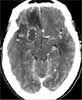

A CT scan of the head reveals several irregular lesions in both cerebral hemispheres and in the right cerebellar hemisphere, with surrounding edema (B).

Oral sulfadiazine and pyrimethamine were started. To rule out CNS lymphoma, a single photon emission CT of the brain was performed. The scan was negative for uptake, consistent with the diagnosis of cerebral toxoplasmosis. A lumbar puncture showed a white blood cell count of 9/μL (with 2% neutrophils, 68% lymphocytes, and 29% monocytes) and a total protein level of 65 mg/dL; the cerebrospinal fluid (CSF) was negative for malignant cells. BK virus, JC virus, and Epstein-Barr virus were not detected. CSF culture yielded no growth.